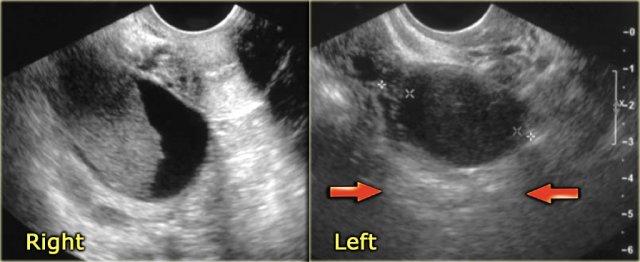

Các hình ảnh siêu âm cho thấy buồng trứng phải và trái: ở cả hai bên đều có hình ảnh trông giống như tổn thương đặc.

Tuy nhiên, có xuyên âm tốt, gợi ý chúng ta có thể đang đối mặt với các nang xuất huyết.

Trên siêu âm Doppler (không hiển thị) không có mạch máu.

Tiếp tục xem kết quả MRI.

Trên hình ảnh chuỗi xung T1W mặt cắt ngang, cả hai tổn thương đều tăng tín hiệu, gợi ý mỡ, máu hoặc dịch giàu protein.

Kỹ thuật xóa mỡ không làm giảm tín hiệu trong các tổn thương này.

Trong một hình ảnh có kỹ thuật xóa mỡ tổng thể tương đối tốt, điều này loại trừ u quái chứa mỡ và xác nhận gợi ý về dịch xuất huyết.

Trên hình ảnh chuỗi xung T2W mặt cắt ngang, cả hai tổn thương đều cho thấy hình ảnh ‘shading’ điển hình.

Sự sụt giảm dần dần tín hiệu T2 được cho là do sự kết hợp của độ nhớt tăng dần và nồng độ protein cùng sắt tăng dần về phía phần thấp của tổn thương.

Không có ngấm thuốc trên hình ảnh trừ (sau tiêm Gd trừ trước tiêm Gd).

Một lần nữa, kỹ thuật trừ rất hữu ích trong các trường hợp như thế này: sự tăng tín hiệu do Gd gây ra trên nền hình ảnh trước tiêm thuốc vốn đã rất sáng sẽ rất khó nhận biết nếu không có kỹ thuật này.